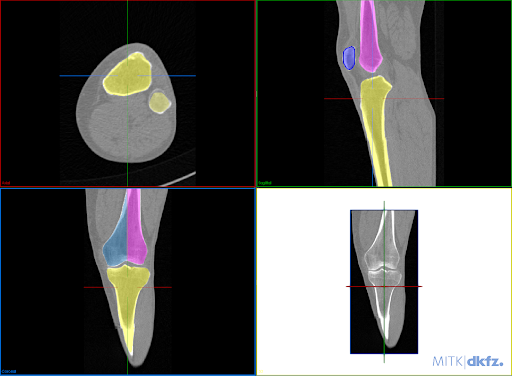

(1) Field-of-view cropping: Prevents superposition of the other laterality in the projection domain. (2) Laterality alignment: Prohibits ambiguities during pose estimation. (3) Definition of 3D reference planes: Two independent raters defined the 3D reference planes in the CT volumes utilizing a DRR preview integrated into the open-source Medical Imaging Toolkit [21] with interactive plane positioning. They serve as ground truth pose reference during simulation. (4) 3D automatic bone segmentation: To compute automatic 3D segmentations, a 3D nnU-Net [9] is trained on a subset of 10 manually annotated CTs for the task of multilabel bone segmentation, segmenting the femur, tibia, fibula, and patella. (5) Suitable segmentation representation: The two femur condyles are not distinguishable in the shape-based representation, however, this is relevant for optimal lateral view recognition. Annotating the condyles as line features would result in an increased manual labeling effort in the projection domain. Alternatively, we propose to incorporate this information in the segmentation by separating the femur annotation symmetrically along the femoral shaft (Fig. 2(a)). This results in one additional segmentation label for the lateral standard to recognize condyles’ congruence and derive the directional pose offset. (6) DRR and mask simulation: DRRs are simulated for varying angulations of orbital and angular rotation around the defined reference standard. The DeepDRR simulation framework was extended to allow the forward projection of corresponding masks (Fig 2(b)).

Fig. 7 shows the importance of individual segmented bone classes on the overall positioning performance evaluated on the test DRRs (3528 DRRs). The fibula has very little influence on the positioning for both views. The patella is only important for the a.-p. view, while tibia and femur are relevant for both views. The condyle assignment for the lateral view determines the rotation direction for the orbital and angular rotation (, ). Inverting the assignment of left and right femur condyle results in a sign flip in , .